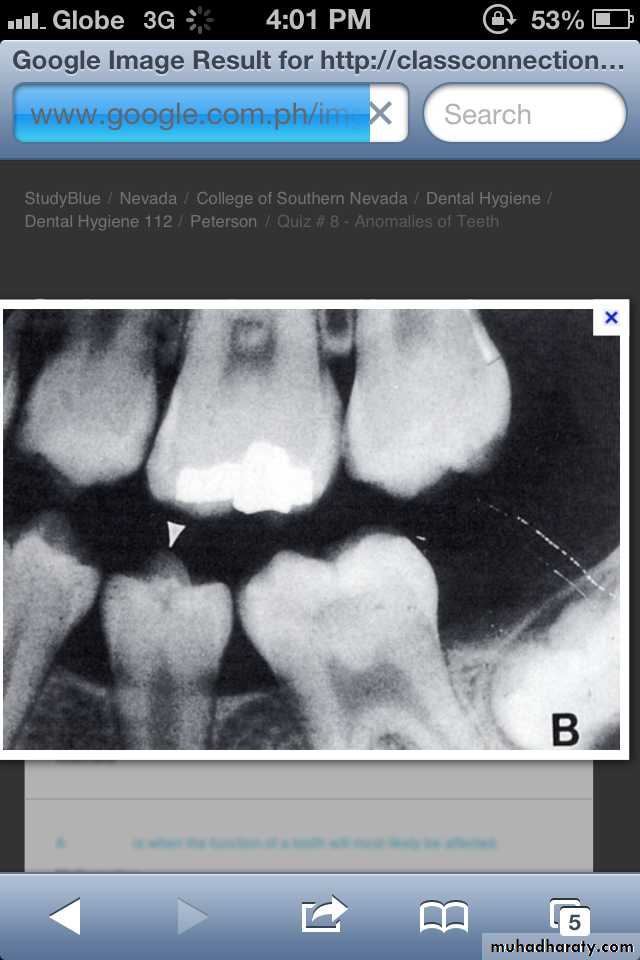

Supernumerary teeth:

Paramolar blocking the eruption of 3rd molar.

MesiodensDistomolars(4th molar)

Mesiodens

Distodens or distomolarParamolar

Supplemental

CAUSE: Is unknown, the tendency is familial. Most cases are polygenetic and represent initial spontaneous gene mutations. When the anomaly is re-stricted to supernumerary teeth, it is inherited as an autosomal recessive trait.

Many supernumerary teeth never erupt, but they may delay eruption of nearby teeth or cause other dental problems.